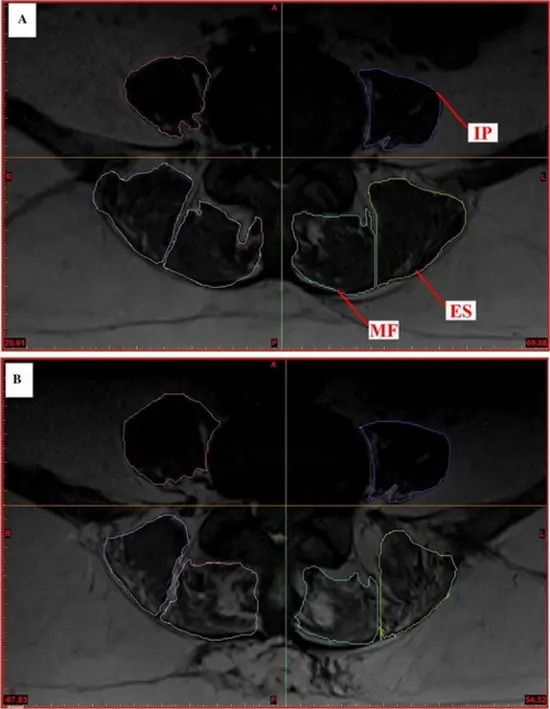

Method: Pre- and postoperative CSAs (~6 months interval) of all paraspinal muscles were measured in six patients undergoing PLS using a 3-T magnetic resonance (MR) scanner to quantify the alterations in geometrical and tissue effective contractile (non-fatty) CSAs of these muscles at all lumbar levels. To examine the presence of any confounding effects on recorded changes within ~7-month period, measurements were also carried out on ten healthy volunteers.

Results: In the healthy population, an important (~22%) portion of CSA of the erector spinae (ES) was noncontractile at the lower lumbar levels. Negligible variations over time in both the total geometrical (<1.7% in average) and contractile (<1.2%) CSAs of muscles were observed in the healthy group (i.e., no confounding effect). Following PLS, significant reductions were observed in the geometrical CSA of only multifidus (MF) muscle by ~14 and 11% as well as in its contractile CSA by ~26 and 14% at the L5-S1 and L4-L5 levels, respectively.

Conclusion: The total CSA of ES at lower lumbar levels shows substantial noncontractile contents in both healthy and patient populations. Biomechanical models of the spine should hence account for the noncontractile contents using only the effective contractile muscle CSAs. Postoperative variations in CSAs of paraspinal muscles may have profound effects on patterns of muscle activities, spinal loading, and stability.